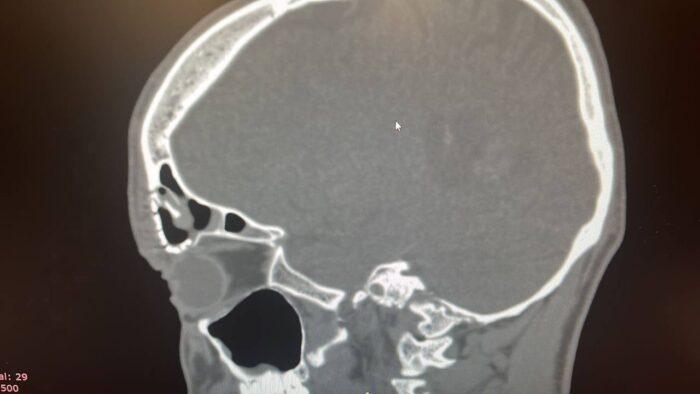

За помощью в оториноларингологическое отделение обратился пациент с переломом передней стенки лобной пазухи после закрытой ЧМТ. Врачи в ходе предоперационного планирования обнаружили серьезные повреждения — значительную линию перелома, вдавление костных отломков в полость пазухи и обширный косметический дефект лобной области.

После проведения компьютерной томографии выяснилось, что местными тканями заместить дефект не получится. Медики приняли решение использовать титановую пластину. Благодаря перфорированной структуре и гибкости она может принимать различные формы и заполнить костный промежуток.

Хирурги успешно провели фронтотомию с ревизией пазухи и пластикой передней стенки лобной пазухи. Операция длилась полтора часа. Врачи ЛОР-отделения удалили костные отломки и заместили обширный костный дефект титановой пластиной, которую прикрепили к костным краям лобной области.